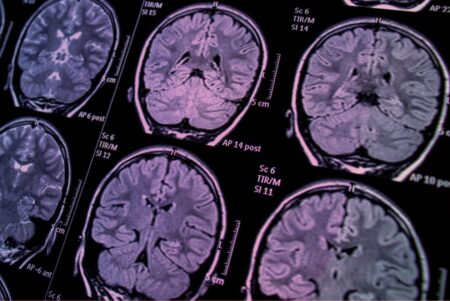

يُنظر إلى التصوير الدماغي اليوم، سواء بالرنين المغناطيسي الوظيفي (fMRI)، أو التصوير المقطعي بالإصدار البوزيتروني (PET)، أو غيرها من التقنيات الحديثة، على أنه أداة دقيقة للكشف عن أسرار العقل البشري. تُعرض الصور الملوّنة في المؤتمرات والبحوث بوصفها “خرائط” تحدد مناطق التفكير والانفعال والإبداع، وتُبنى عليها نظريات حول الذكاء، والانحراف، والمرض النفسي، بل وتُستخدم لتبرير العقاقير والعلاجات السلوكية. لكنّ هذه التقنية تقوم على افتراضٍ فلسفيٍّ غير معلن: أن هناك دماغًا طبيعيًا تُقاس عليه بقية الأدمغة، وأن أي انحراف عن متوسط هذا النموذج يُعد خللًا أو اضطرابًا.

يُنظر إلى التصوير الدماغي اليوم، سواء بالرنين المغناطيسي الوظيفي (fMRI)، أو التصوير المقطعي بالإصدار البوزيتروني (PET)، أو غيرها من التقنيات الحديثة، على أنه أداة دقيقة للكشف عن أسرار العقل البشري. تُعرض الصور الملوّنة في المؤتمرات والبحوث بوصفها “خرائط” تحدد مناطق التفكير والانفعال والإبداع، وتُبنى عليها نظريات حول الذكاء، والانحراف، والمرض النفسي، بل وتُستخدم لتبرير العقاقير والعلاجات السلوكية. لكنّ هذه التقنية تقوم على افتراضٍ فلسفيٍّ غير معلن: أن هناك دماغًا طبيعيًا تُقاس عليه بقية الأدمغة، وأن أي انحراف عن متوسط هذا النموذج يُعد خللًا أو اضطرابًا.

من الناحية التقنية يعتمد التصوير الدماغي على قياس تدفق الدم أو نشاط الخلايا العصبية في مناطق معينة أثناء أداء مهمة معرفية أو انفعالية. في التجارب تُقاس هذه الأنشطة عند مجموعة من الأفراد، ثم تُقارن بنتائج مج وعة أخرى يُفترض أنها “طبيعية”، فيُستنتج أن ارتفاع النشاط في منطقة معينة يعني “خللًا” أو “نقصًا” في الوظيفة.

التصوير الدماغي الحديث لا يقيس الأفراد، بل المتوسطات. في دراسة على مئة شخص، يُجمع النشاط الدماغي، ثم يُستخرج متوسط النشاط في كل منطقة، وتُقارن به الحالات الأخرى. لكن المتوسط ليس إنسانًا، بل رقمًا رياضيًا، لا يمثل أية بنية واقعية. ولأن البشر لا يتطابقون في بنائهم العصبي، فإن هذا المتوسط يفقد دقته العلمية عند تطبيقه على الفرد. كل صورة دماغية تُظهر “انحرافًا عن المتوسط” هي في الحقيقة إثبات للفردانية العصبية، لا دليلاً على المرض. غير أن العلم التقليدي يقرأها بالعكس تمامًا.